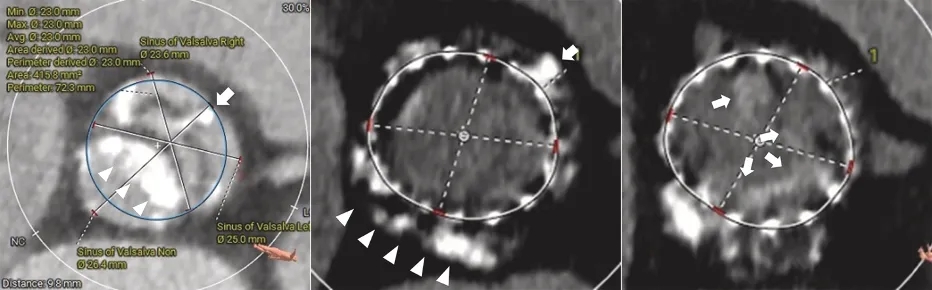

首次TAVR术前CT提示,患者为I型二叶式主动脉瓣,左、右冠瓣融合,并可见钙化嵴(图3,左)。同时可见无冠瓣瓣叶严重钙化(图3,左)。主要测量参数如下:

• 主动脉瓣环(Annulus):24.9×18.9mm,面积 373.8mm²,周长69.7mm。

• 左心室流出道(LVOT):26.8×18.5mm,面积 373.9mm²,周长70.8mm。

• 窦管交界(STJ):25.2×23.0mm。

• Valsalva 窦:左冠窦25.0mm,右冠窦23.6mm,无冠窦26.4mm。

• 冠脉开口高度:左冠14.4 mm,右冠13.2 mm。

图 3 术前CT 影像

(左)首次 TAVR 前CT显示 1 型双叶主动脉瓣,左、右冠瓣融合,并可见钙化嵴(白色箭头);同时可见无冠瓣瓣叶严重钙化(白色箭头)。(中)redo-TAVR 前CT于既往 Evolut R 瓣膜支架的 node 4 层面显示,由于瓣叶(白色箭头)及钙化嵴(白色箭头)存在严重钙化,导致既往瓣膜支架呈椭圆形扩张。(右)redo-TAVR 前 CT 于既往 Evolut R 瓣膜支架的 node 5 层面显示,既往瓣膜瓣叶存在严重钙化(白色箭头)。

redo-TAVR 前的CT显示,由于严重的瓣叶钙化及钙化嵴存在,既往 Evolut R 瓣膜支架呈椭圆形扩张(图3,中)。此外,既往植入瓣膜的瓣叶亦可见明显的重度钙化(图3,右)。